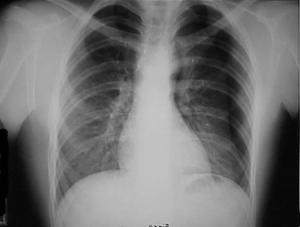

Pneumotorace sufocant bilateral Pneumotorace sufocant stang

Pneumotorace

sufocant stang Pneumotorace

sufocant drept Pneumotorace

sufocant drept

Imagine

CT Imagine CT